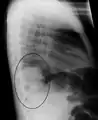

Right upper lobe pneumonia as marked by the circle.